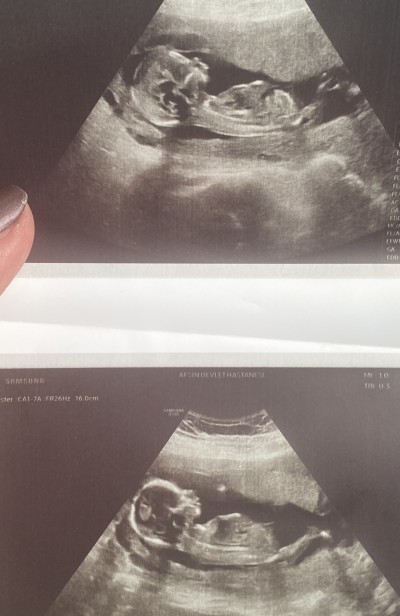

Kızlar 17. Haftama girdim ve cinsiyet hala belli değil o kadar merak ediyorum ki. Ben ultrosana bakınca kız hissediyorum sizin de hislerinizi merak ettim:)

image